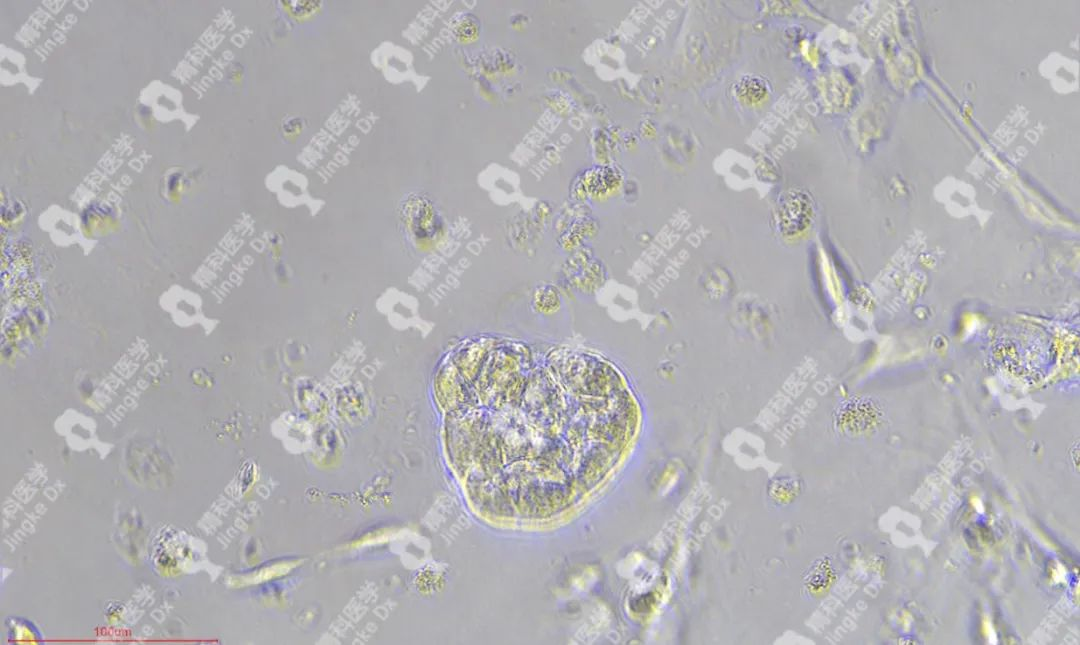

精科類器官培養(yǎng)相關(guān)服務(wù) 精科醫(yī)學(xué)作為類器官技術(shù)轉(zhuǎn)化先行者致力于推動(dòng)類器官技術(shù)的轉(zhuǎn)化與應(yīng)用,對(duì)基于類器官培養(yǎng)擁有成熟的技術(shù)與經(jīng)驗(yàn)。精科類器官團(tuán)隊(duì)技術(shù)深耕十余年,擁有國(guó)內(nèi)頂級(jí)的類器官團(tuán)隊(duì),超微量建模技術(shù)成功率高達(dá)95%以上,有成功建模30+種腫瘤的經(jīng)驗(yàn)(包括上述子宮內(nèi)膜癌、宮頸癌和卵巢癌)??梢蕴峁┌惼鞴俳Ec保存(建模、凍存、傳代)、類器官檢測(cè)(類器官H&E染色、免疫組化、藥物敏感度篩選)等多種類器官相關(guān)服務(wù)。檢測(cè)服務(wù)最快可在十個(gè)工作日內(nèi)完成,更好為患者爭(zhēng)取治療時(shí)間。 ★ PIC.01 精科卵巢癌類器官圖像 ★ PIC.02 精科宮頸癌類器官圖像 ★ PIC.03 精科子宮內(nèi)膜癌類器官圖像